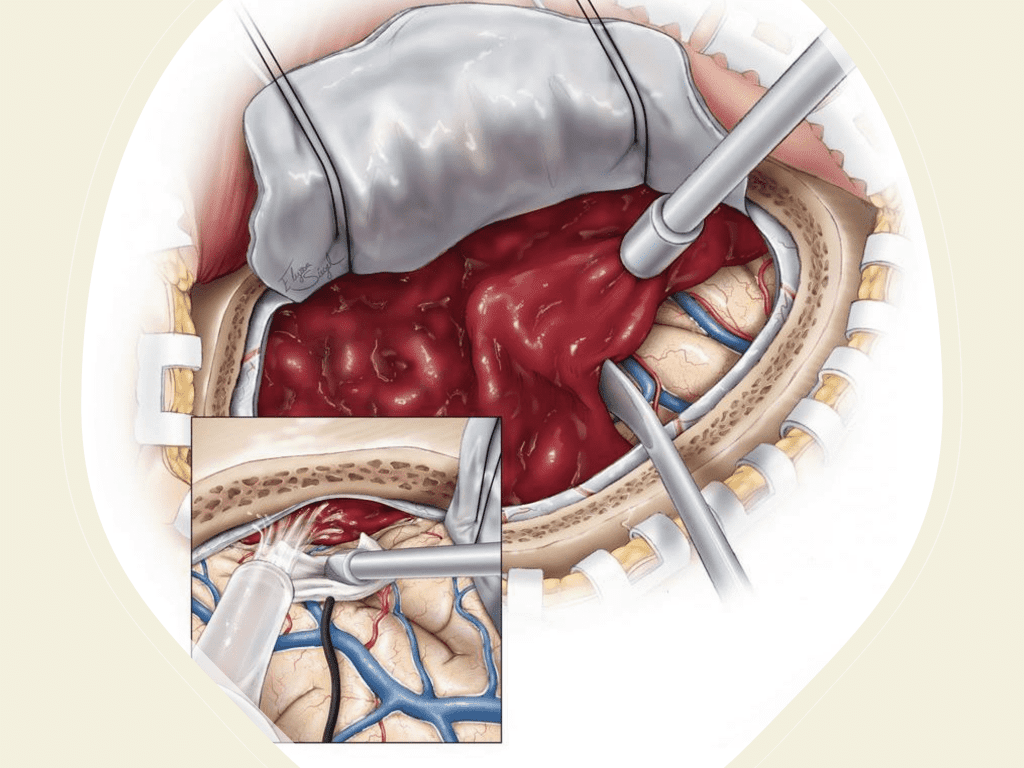

A woman in her 80s developed mild dizziness and headache following incidental trauma working in her garage one day. She presented several weeks later to the ER and was diagnosed with bilateral subdural hematomas, which were initially managed with observation, low dose Decadron, considering the mildness of symptoms, advanced age, and history of CLL with thrombocyptopenia (<100k). Over the next 4 weeks, the collections remained relatively stable with evidence of slight growth (10 to 12 mm thickness, and 2 mm right to left shift) on NCT (Figure 1. A and B).

Figure 1. A) 6 weeks post mild trauma B) 4 weeks post mild trauma demonstrates stable subacute subdural collections with mild growth and sulcal effacement.

The treatment and management of cSDH remains controversial and has traditionally been treated either conservatively with observation and serial imaging in asymptomatic patients and smaller collections (without midline shift) or more aggressively with surgical evacuation in symptomatic patients or larger collections (with greater than 5 mm of midline shift). There is a variety of surgical options for cSDH treatment including twist-drill craniotomy (5-10 mm incision) with or without a subdural evacuating port system (SEPS), burr hole evacuation (silver dollar or up to 30mm incision) with or without drains, or craniotomy (>30 mm incision). Irrespective of the type of evacuation, cSDH surgical treatment continues to have high recurrence rates ranging from 5% to 37%, thereby subjecting these patients to repeat surgical interventions, hospital admissions, and the associated complications including peri-operative morbidity, diminished neurologic and functional status, and even mortality (5).

Figure 6. Surgical craniotomy for Subdural Hematoma. (https://www.neurosurgicalatlas.com/volumes/emergency-neurosurgery-and-trauma/traumatic-hematoma/acute-subdural-hematoma((c)2022, The Neurosurgical Atlas) (6).